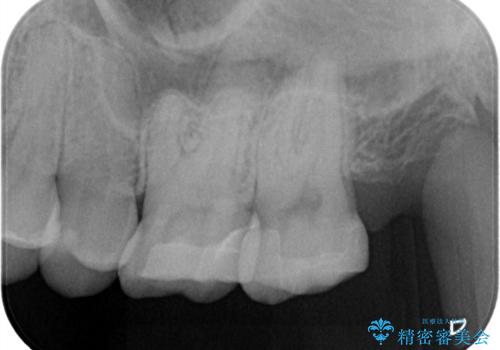

【セラミックインレー】適合の良いセラミックインレーを入れたい。

- 毎回フロスが引っかかることを気にされており、改善のため適合の良いセラミックインレーで修復しました。

以前に他院で詰め物をいれた時は、フロスが毎回ちぎれて大変だったそうですが改善して喜んでおられました。